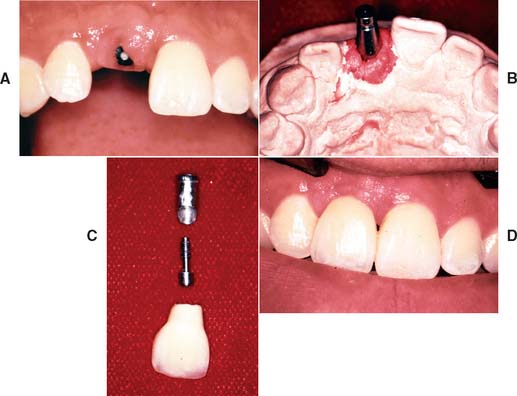

Today the continued high rate of success achieved with osseous integrated dental implants allows a greater number of patients to enjoy the benefits of fixed rather than removable dental prostheses.1-3 The main indications for implant-supported restorations in the partially edentulous patient are the free-end distal extension, in which no posterior abutment is available (Fig. 13-1), and the long edentulous span. In both these situations, the conventional dental treatment plan would include a partial removable dental prosthesis. However, with the advent of dental implants, the patient can benefit from fixed restorations. In addition, in the short edentulous span, the single dental implant is a popular option (Fig. 13-2).

Fig. 13-2 A, Single-tooth implant with an internal anti-rotational feature. B, Implant crown replacing a single missing tooth (cement retained).

The use of single implants in restoring missing teeth is an attractive option for the patient and the dentist. However, it requires careful implant placement and precise control of all prosthetic components. Single-tooth restorations supported by implants may be indicated in the following situations:

Several systems have been developed to comply with these demands. Common indications include congenitally missing maxillary lateral incisors (Fig. 13-42) and teeth in which endodontic treatment was unsuccessful (Fig. 13-43). Screw loosening has most commonly been associated with the terminally positioned single molar implant crown (Fig. 13-44).